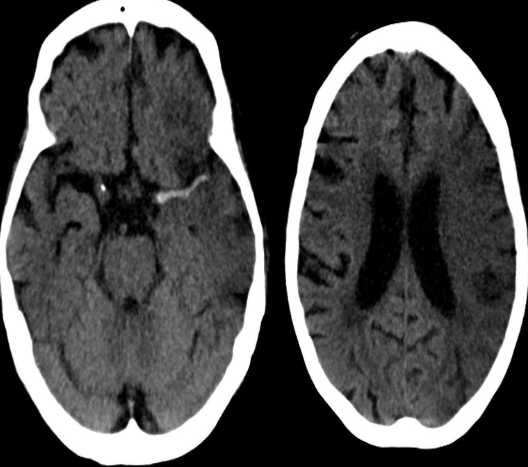

CT Brain IN EMERGENCY

Epidural hematoma

- Convex inner margin (lens-shaped)

- High density area

CT brain - Acute subdural hemorrhage

- crescent shape

CT brain - Chronic subdural hemorrhage

- Concave

CT brain - Acute on chronic subdural hematoma

- Inner margins are concave

A. Imaging study. *CT head *(without contrast; axial plane)

B. What is the most likely diagnosis? Subarachnoid hemorrhage

- Multiple areas of high attenuation in the basal cisterns, Sylvian fissures, and sulci are

- characteristic of extensive subarachnoid hemorrhage.

Intra ventricular hemorrhage

- Anterior/Posterior Horns hemorrhages

- 3rd ventricles

Subacute subdural hematoma

- Shifting + Isodensity ~~ SOL

Intracerebral hemorrhage

Infarction appear hypodense on CT without contrast

Sign? Hyperdense sign in stroke; LT Middle cerebral artery hyperintense

Y

Dense basilar artery and middle cerebral arteries on CT

Thrombus in vessel is hyperdense relative to flowing blood